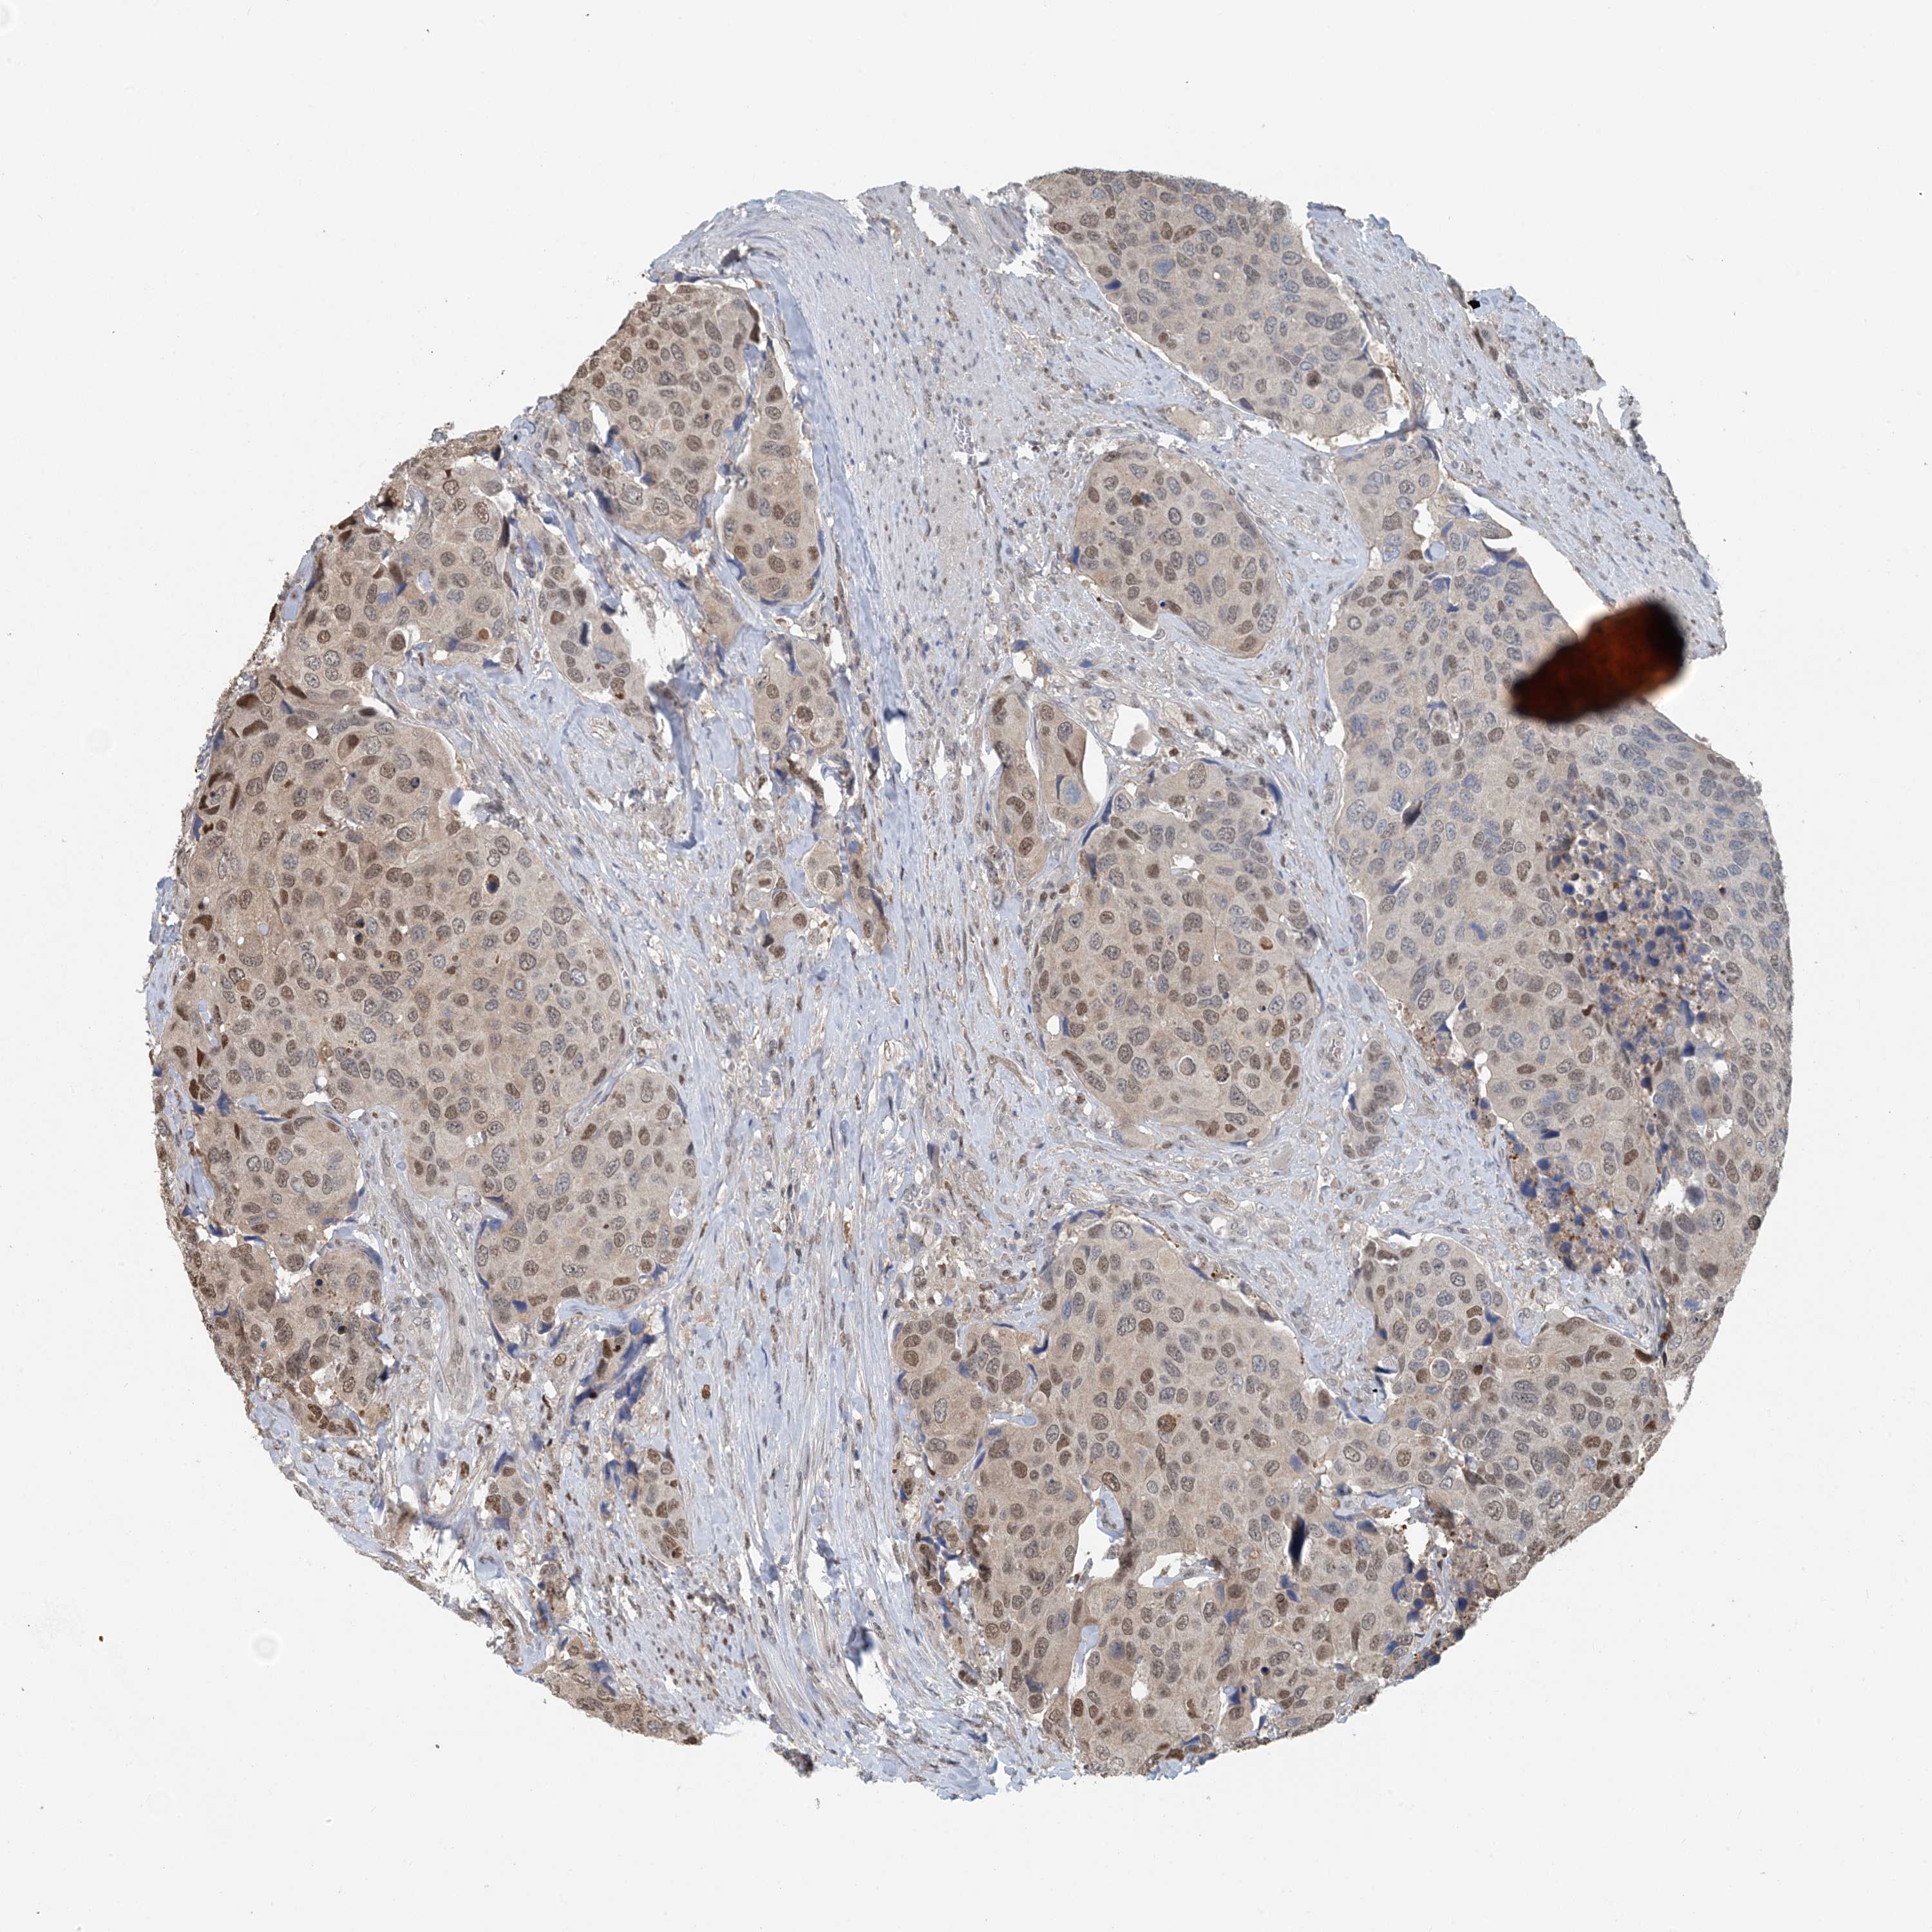

UROTHELIAL CANCER - Protein expressioni

A mouse-over function shows sample information and annotation data. Click on an image to view it in a full screen mode. Samples can be filtered based on level of antibody staining by selecting one or several of the following categories: high, medium, low and not detected. The assay and annotation is described here.

Note that samples used for immunohistochemistry by the Human Protein Atlas do not correspond to samples in the TCGA dataset.

Antibody stainingi

Antibody staining in the annotated cell types in the current human tissue is reported as not detected, low, medium, or high, based on conventional immunohistochemistry profiling in selected tissues. This score is based on the combination of the staining intensity and fraction of stained cells.

Each image is clickable and will lead to virtual microscopy that enables deeper exploration of all samples and also displays staining intensity scores, fraction scores and subcellular localization as well as patient and tissue information for each sample.

Antibody HPA035063

Antibody HPA035064

Urothelial carcinoma, High grade

Urothelial carcinoma, Low grade